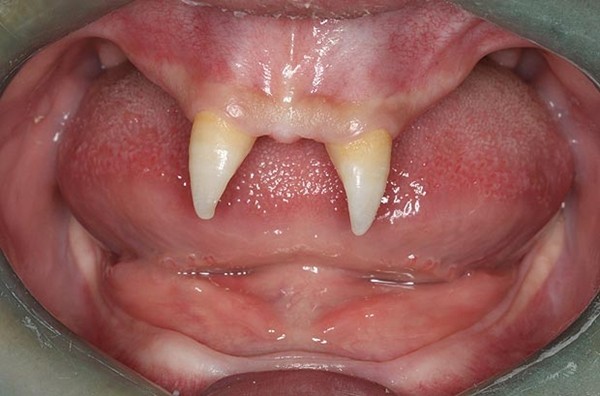

Một cậu bé 16 tuổi tên Wang Pengfei sống tại Trùng Khánh, Tây Nam Trung Quốc đă mắc một chứng bệnh lạ từ khi sinh ra. Căn bệnh này khiến Pengfei có rất ít tóc và đến thời kỳ mọc răng, cậu chỉ mọc duy nhất 2 chiếc răng cửa sắc nhọn như… ma cà rồng.

Hàm răng kỳ lạ của Wang Pengfei chỉ có duy nhất 2 chiếc răng cửa nhọn hoắt.

Do căn bệnh này, cuộc sống của Wang Pengfei gặp rất nhiều khó khăn. Bên cạnh đó, t́nh cách củaPengfei cũng trở nên kỳ quặc, Bà Wang Hui cho biết: “Từ nhỏ, Pengfei đă không có bạn và khi lớn lên nó mới nhận ra ḿnh khác biệt với người khác. Con trai tôi này càng cô lập với mọi người. Nó luôn thấy xấu hổ về hàm răng của ḿnh và thậm chí sẵn sàng tấn công những ai trêu chọc hay bàn tán về nó”.

Trong khi đó, các bác sĩ ở bệnh viện Tây Nam cho biết, chỉ khi nào Pengfei đủ tuổi trưởng thành mới có thể tiến hành phẫu thuật. Dự kiến chi phí cho ca phẫu thuật này là khoảng 70.000 đến 80.000 nhân dân tệ (khoảng 234 đến 269 triệu VNĐ).